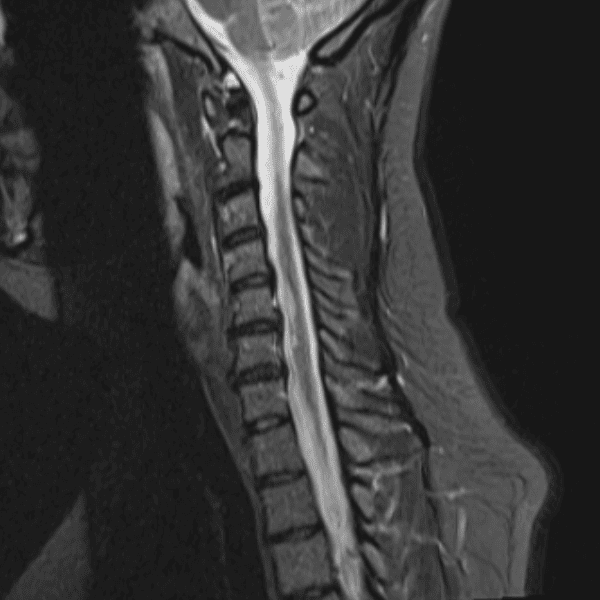

Simulates call by including subtle or difficult cases and some normals.

35 cases